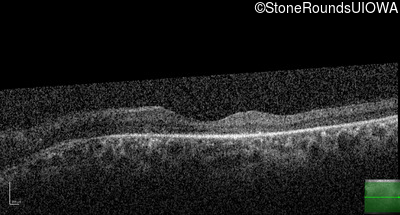

Optical Coherence Tomography - Left - 20/32

Exemplar / OCT Stack

OCT Stack